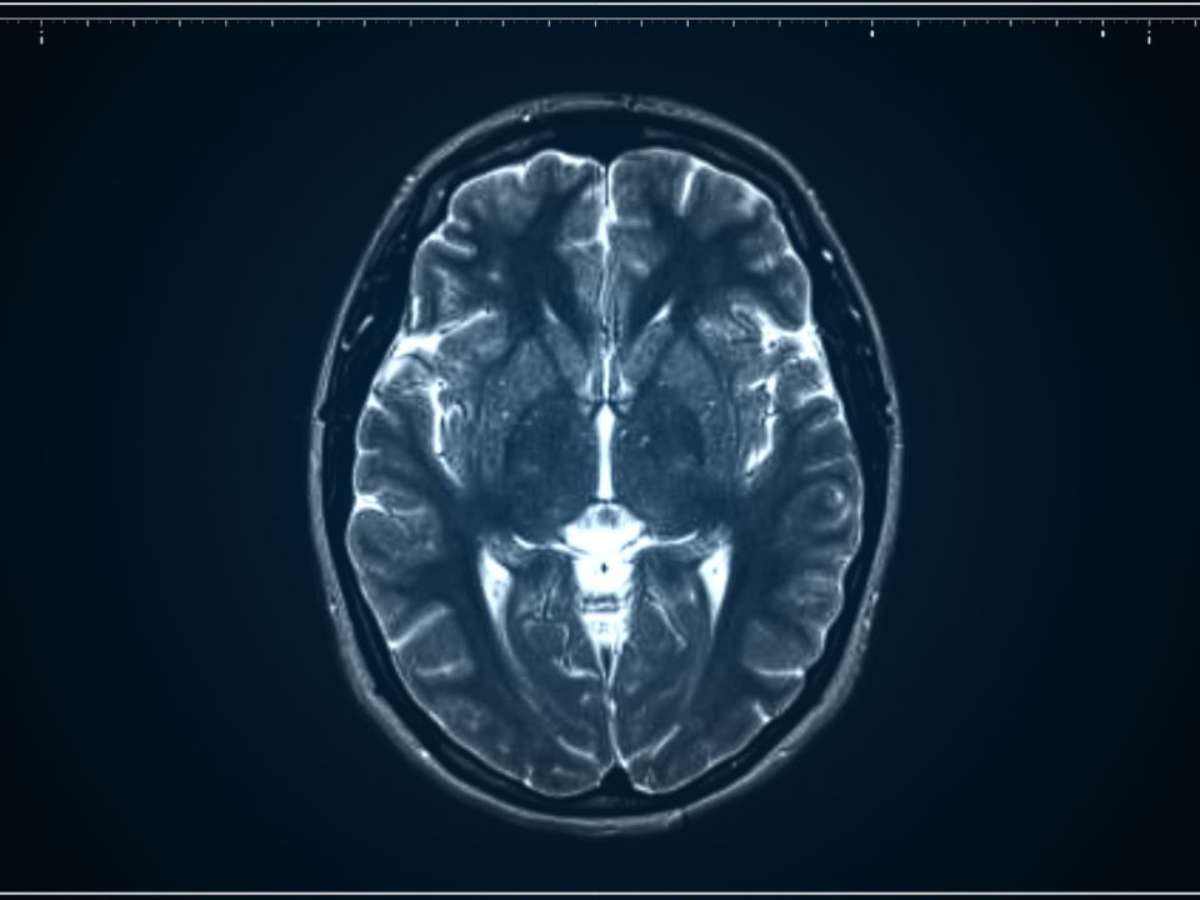

Com apoio de imagens de ressonância magnética e aprendizado de máquina, cientistas descobriram diferentes “biótipos” de depressão; entenda

Foto: Reprodução: Canva/AlpakaVideo / Bons Fluidos

Pesquisadores da Stanford Medicine estão desenvolvendo um método inovador capaz de identificar diferentes "biótipos" da depressão com o auxílio de exames de imagem cerebral. A ideia é simples e revolucionária: mapear o funcionamento do cérebro para entender quais circuitos estão em desequilíbrio. Dessa forma, é possível personalizar o tratamento de cada paciente.

Usando ressonância magnética funcional (fMRI) e técnicas de aprendizado de máquina, a equipe de Stanford analisou centenas de cérebros e encontrou seis subtipos diferentes de depressão, cada um ligado a um circuito cerebral específico. Entre eles estão os circuitos responsáveis pela atenção, emoção, prazer e controle cognitivo - áreas que, quando alteradas, geram sintomas distintos como apatia, tristeza intensa, ansiedade ou dificuldade de concentração.